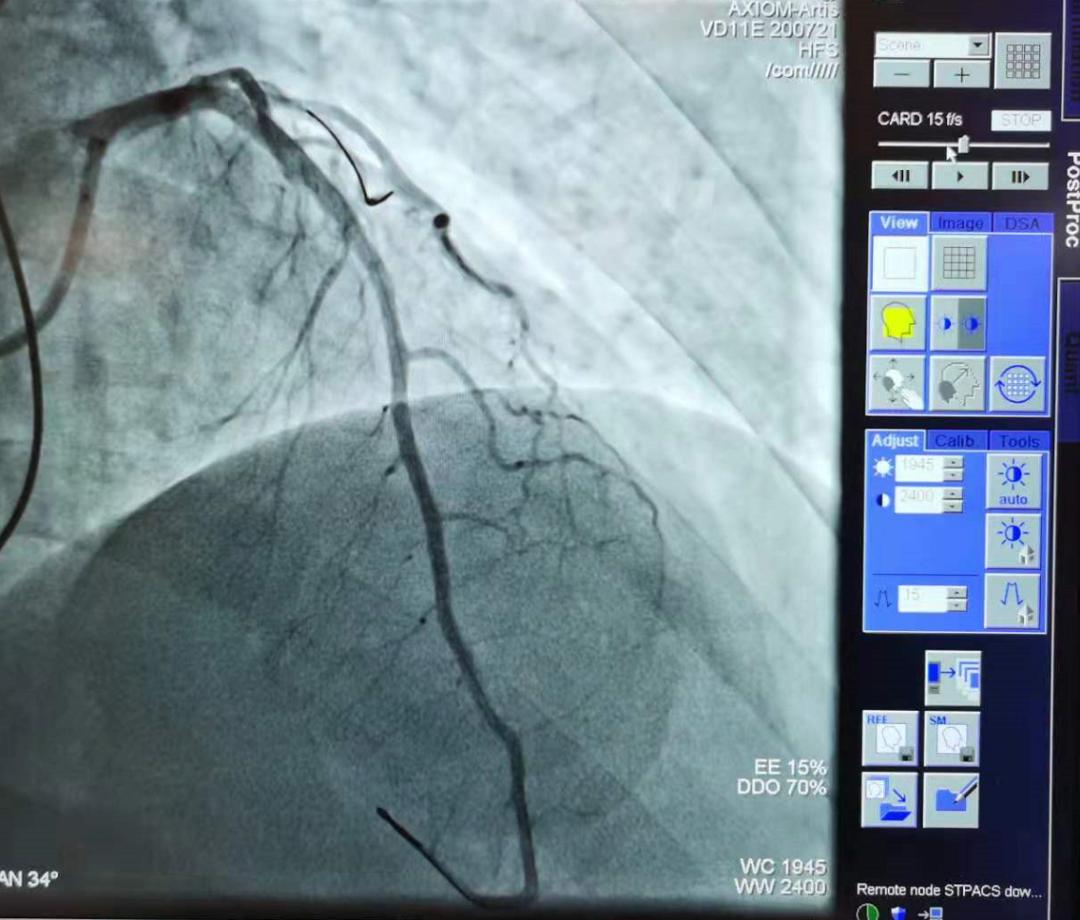

手术后,冠状动脉前降支开通